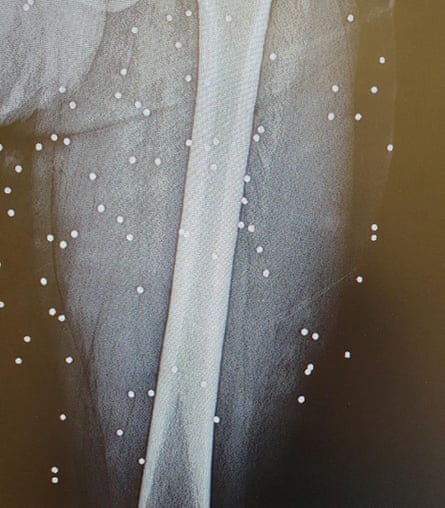

Up until a few hours earlier, doctors and patients were still sending me photos on WhatsApp; pellet wounds to the back, the hands, the head. Painful injuries, frightening injuries – but survivable. The kinds of wounds that could be treated, that suggested the violence still had limits. Then, at eight o’clock, everything went dark. Internet, mobile phones, messages, maps – all gone.

The patients coming in now were not hit by pellets – they had been shot with live ammunition. War bullets. These were not warning shots. These were bullets designed to pass through the body. Bullets that entered on one side and exited from the other.